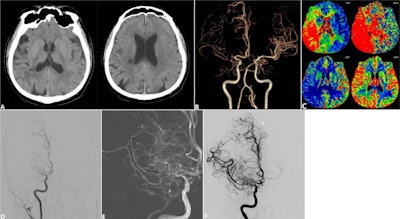

Images depict a 54-year-old male patient with nonacute right middle cerebral artery occlusion show anterior circulation symptomatic nonacute intracranial artery occlusion at imaging screening and endovascular recanalization. (A) Axial non-contrast CT images show infarction in the right middle cerebral artery territory with an Alberta Stroke Program Early CT score of 8. (B) CT angiographic image shows occlusion of the right middle cerebral artery. (C) Axial CT perfusion images show hypoperfusion in the right middle cerebral artery territory. (D) Baseline angiography confirmed right middle cerebral artery occlusion with an American Society of Intervention and Therapeutic Neuroradiology/Society of Interventional Radiology collateral grade of 2. (E) Intraprocedural angiography showed balloon angioplasty being performed at the occluded segment. (F) Postprocedural angiography demonstrated successful recanalization of the occluded artery after balloon angioplasty (Expanded Treatment in Cerebral Infarction, known as eTICI, grade 3 with residual stenosis of 30%), and thus no stent was used.Images depict a 54-year-old male patient with nonacute right middle cerebral artery occlusion show anterior circulation symptomatic nonacute intracranial artery occlusion at imaging screening and endovascular recanalization. (A) Axial non-contrast CT images show infarction in the right middle cerebral artery territory with an Alberta Stroke Program Early CT score of 8. (B) CT angiographic image shows occlusion of the right middle cerebral artery. (C) Axial CT perfusion images show hypoperfusion in the right middle cerebral artery territory. (D) Baseline angiography confirmed right middle cerebral artery occlusion with an American Society of Intervention and Therapeutic Neuroradiology/Society of Interventional Radiology collateral grade of 2. (E) Intraprocedural angiography showed balloon angioplasty being performed at the occluded segment. (F) Postprocedural angiography demonstrated successful recanalization of the occluded artery after balloon angioplasty (Expanded Treatment in Cerebral Infarction, known as eTICI, grade 3 with residual stenosis of 30%), and thus no stent was used.RSNA